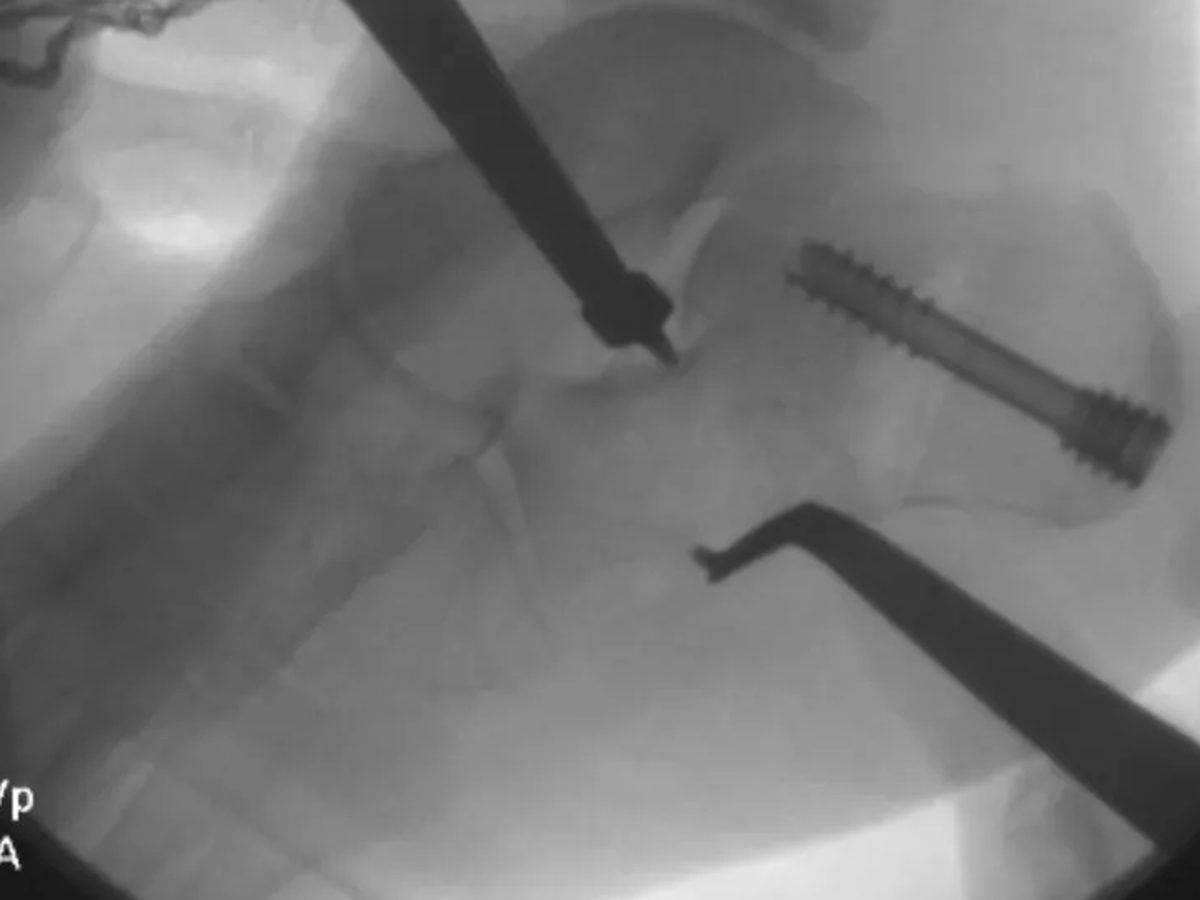

Hailey’s surgery went well, and we are incredibly thankful for all the love, prayers, and support we've received.